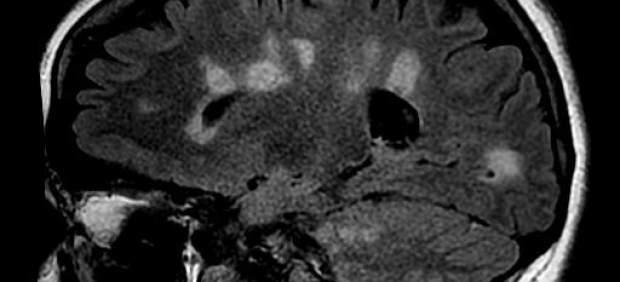

En la esclerosis múltiple se verifica un daño y una pérdida de mielina en varias áreas -de ahí el nombre de múltiple- del sistema nervioso central. Numerosas evidencias sean clínicas o experimentales indican que existe un proceso de desmielinización que determina daños o pérdida de la mielina y la formación de lesiones (placas).

Estas pueden cambiar de una fase inflamatoria inicial a una crónica, en la cual provoca características similares a las cicatrices, de ahí la denominación 'esclerosis', que significa "endurecimiento patológico de un órgano o tejido".